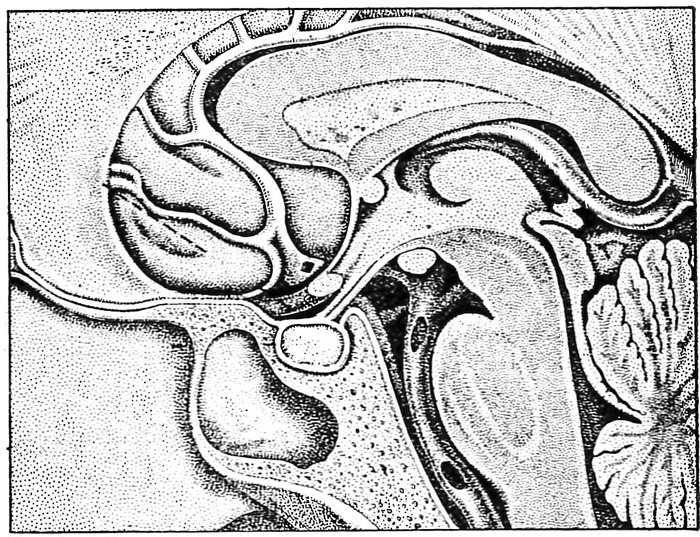

Figure 2: Lateral view of the anatomy of the pituitary fossa, visual pathway and third ventricle [2].

Figure 2 shows the anatomy of the pituitary fossa and gland and their relation to the visual pathway above. The fossa is covered by the diaphragma sellae which is perforated by the pituitary stalk which along with the optic nerve and chiasma above are surrounded by cerebrospinal fluid (CSF) in the chiasmatic cistern. The chiasma is usually situated directly above the centre of the fossa in the floor of the third ventricle and is 5-10mm above the fossa so that a pituitary tumour has to expand out of the fossa, fill up the CSF space above and thus be of substantial size before it impinges upon the visual system. Because of the partial decussation of the visual axons in the chiasma (Figure 3) the crossing nasal fibres are first involved, producing the classical bitemporal visual field defects of compression from a pituitary tumour.